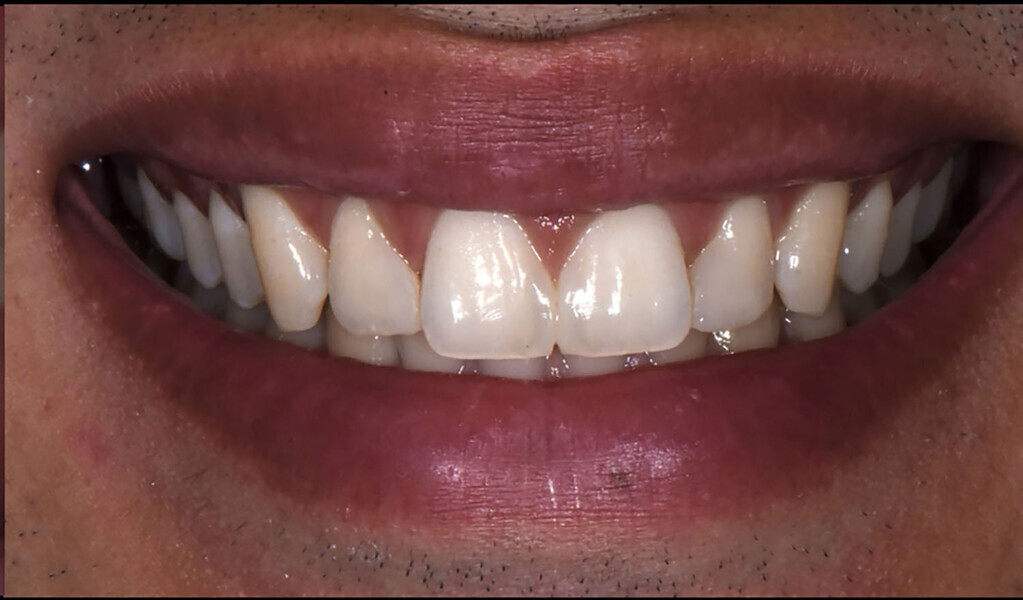

The patient presented with spaces between teeth #11 and 21 and between teeth #12 and 11. During the diagnostic phase, a digital screening of the smile line was carried out. The treatment involved the closure of the anterior spaces with a direct technique using a nano-hybrid composite. The operative steps to close the gap between teeth #11 and 21 provide photographic guidelines on a direct technique presented here with the name: “two-matrix technique” for diastema closure.

Clinical history The patient came to the initial dental consultation for an aesthetic assessment. The patient was in good health without any systemic conditions and had never undergone any orthodontic treatment. The treatment steps necessary to improve the aesthetics were explained to the patient after a careful diagnosis. The patient desired complete closure of the anterior spaces for aesthetic purposes.

Record taking and diagnosis On clinical examination, there were no signs of structural impairment related to previous treatments. On radiographic examination of the crowns, pulps, roots and periodontium, there were no findings. The diagnosis was a diastema between teeth #11 and 21 and minimal gap between teeth #12 and 11.